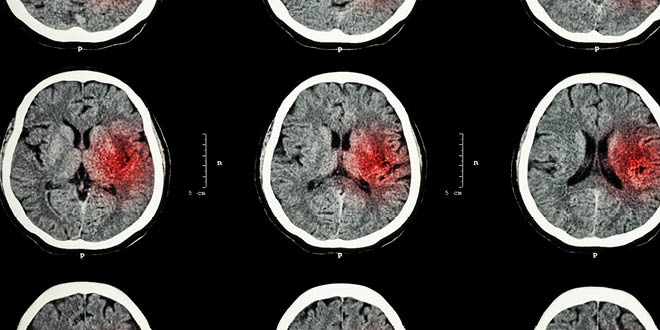

These findings are based on a study of 26,000 people around the world. It was conducted by researchers of the Population Health Research Institute (PHRI) of McMaster University. Stroke is one of the biggest causes of death and disability, especially in low income and middle income countries. There are two major types of stroke: ischaemic stroke and hemorrhagic stroke. Ischaemic stroke is where a blood clot blocks a blood vessel. These are responsible for 85 percent of all strokes. Hemorrhagic strokes occur when there is bleeding into the brain and account for 15 percent of strokes.